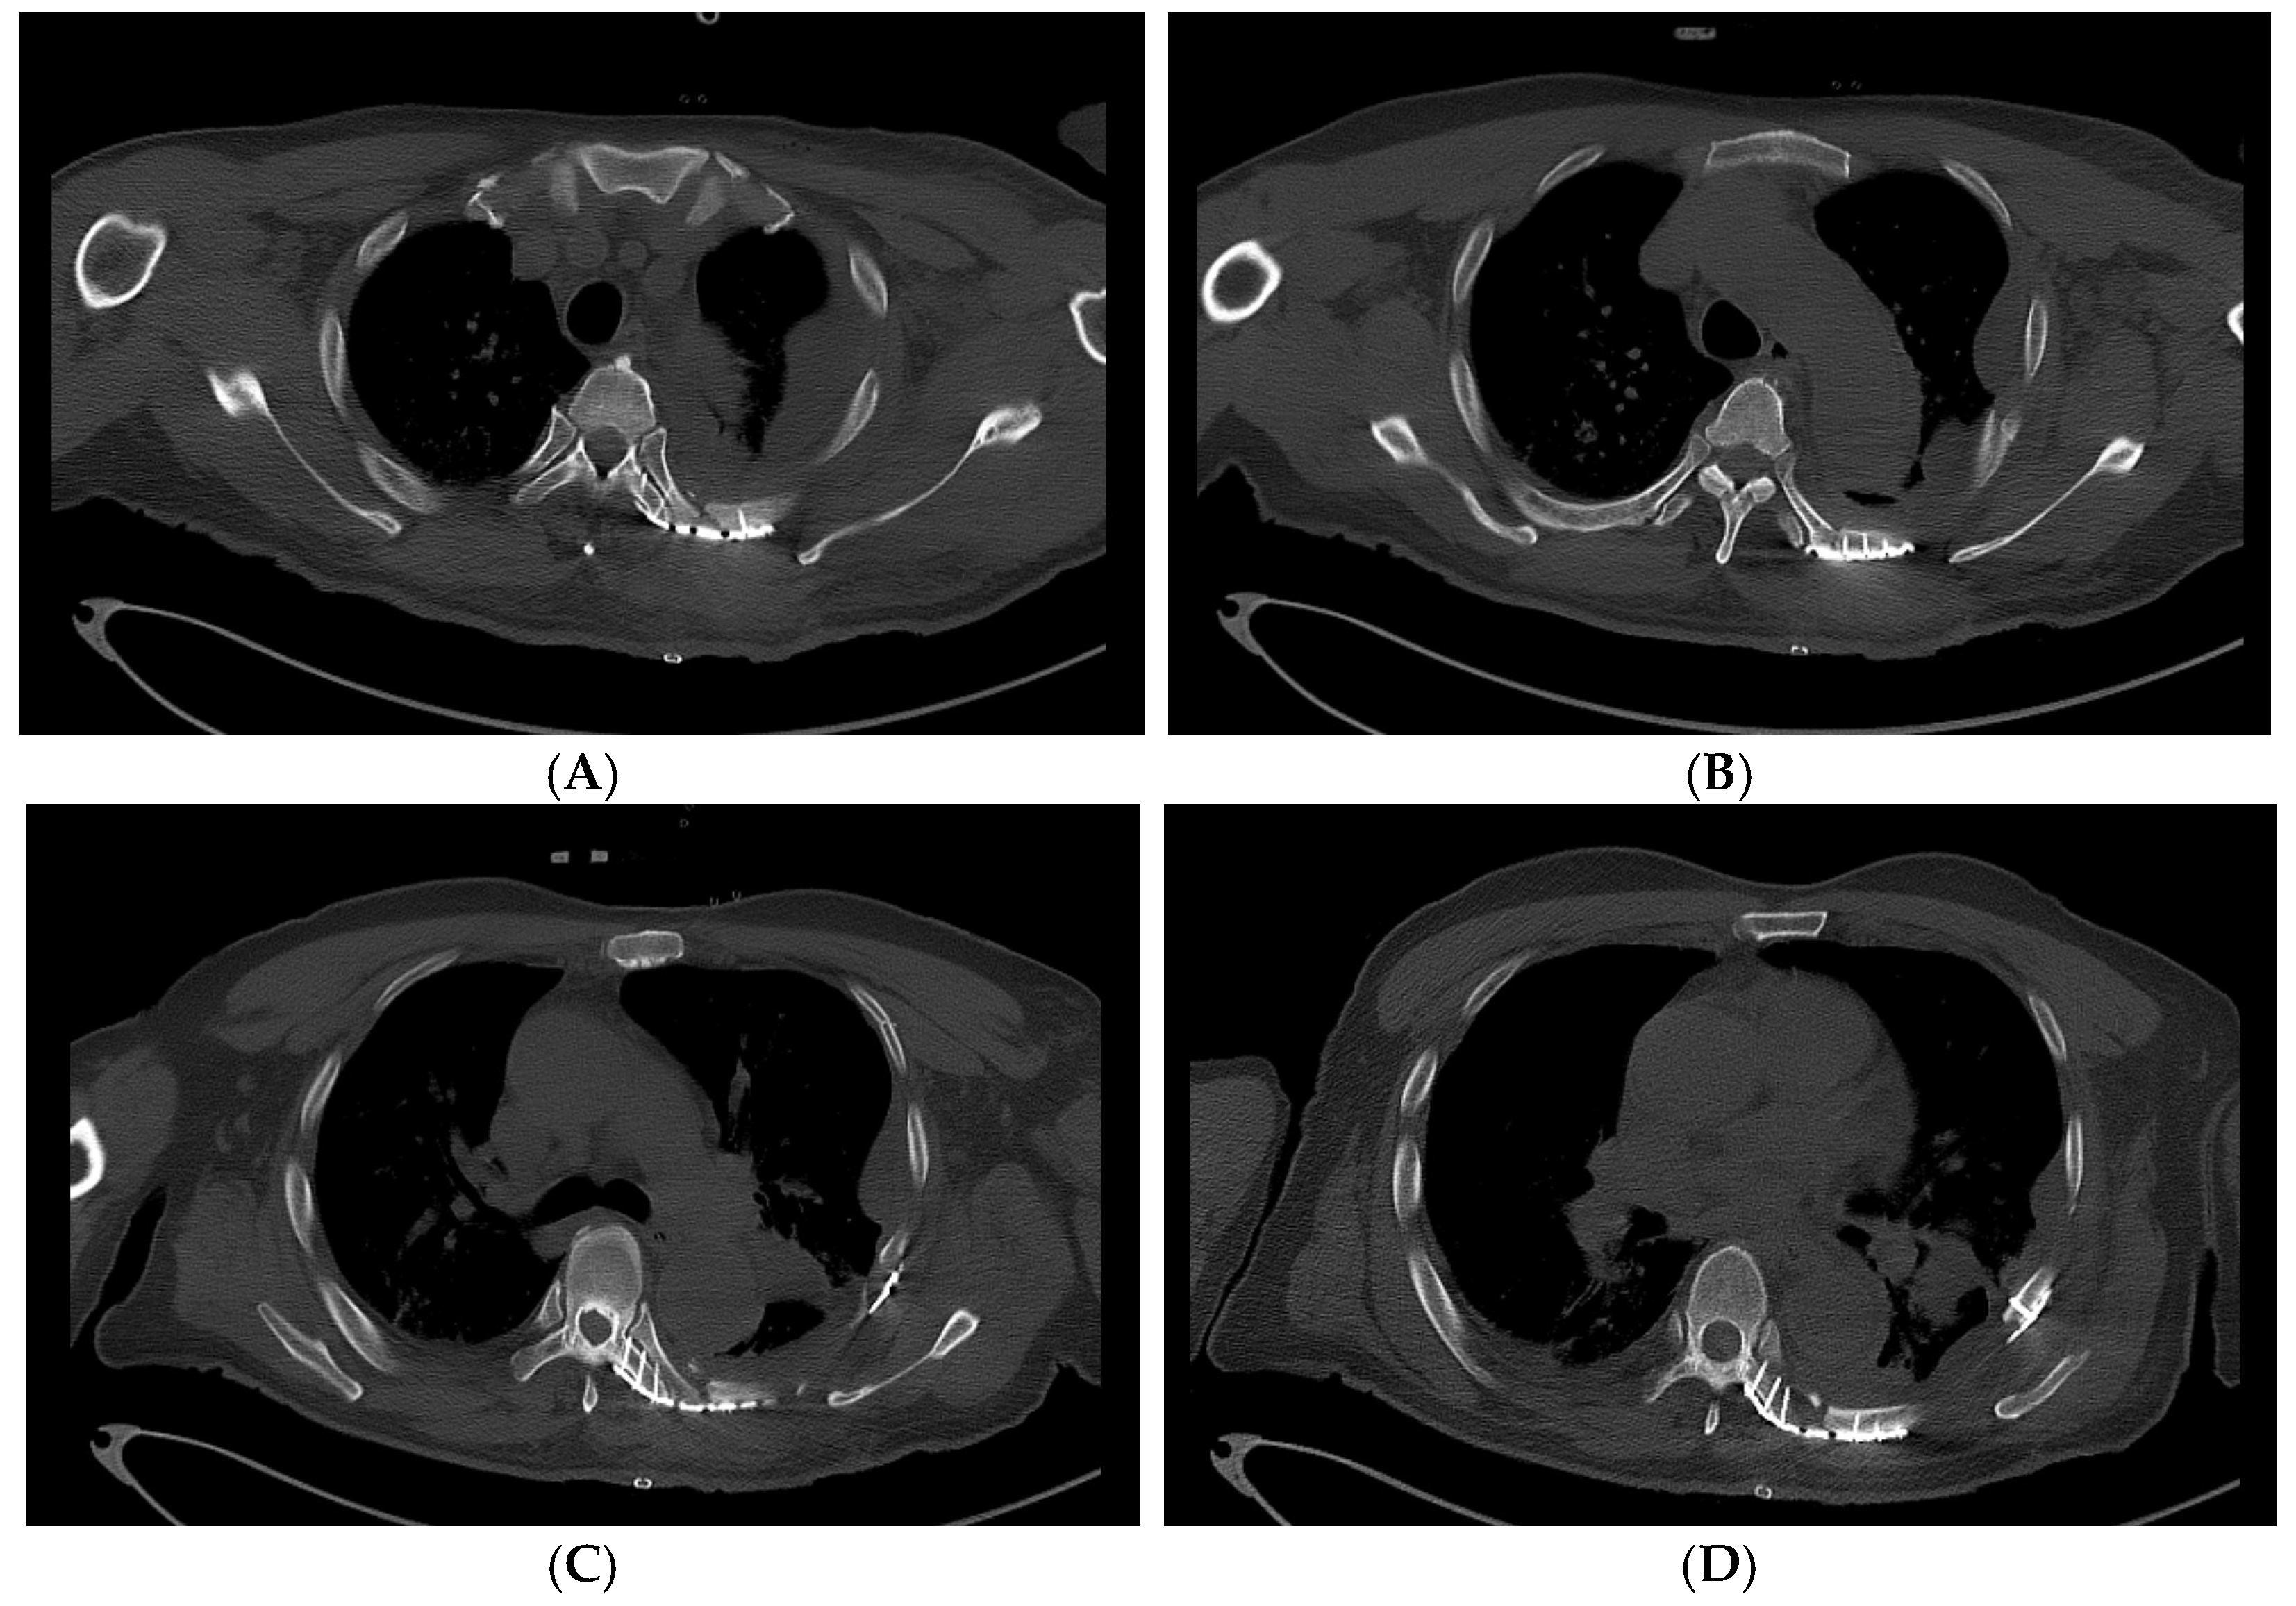

Due to the significant pulmonary contusion and dyspnea, the patient’s oxygen saturation dropped below 90% after WBCT was taken, and he was intubated and initially placed on ventilatory support. A thoracic trauma surgeon was consulted due to the radiologic flail chest, resultant respiratory compromise, and displaced posterior rib segments threatening the patient’s descending aorta. Early surgical stabilization was scheduled. The following day, rib CT was performed for surgical planning (Figure 2), and the patient was taken to the operating room for surgical stabilization of the rib fractures.

Figure 2. 3D reconstructed images of the rib CT taken on HD #2 for operative planning. Anteroposterior (A), left oblique (B), and posteroanterior (C) views of the 3D reconstruction images show a radiological flail chest with posterior paraspinal fractured fragments.